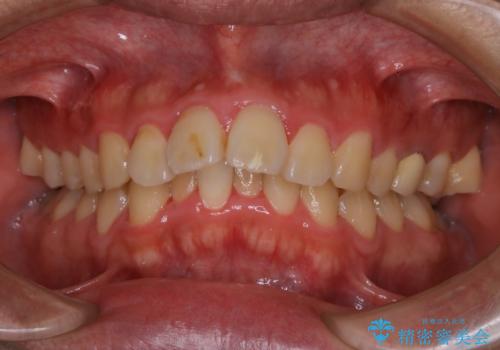

- 上顎前歯の突出感と下顎前歯のガタつきが主訴で来院されました。

出っ歯とガタつきの改善を行うには抜歯が必要と診断し、上下左右第一小臼歯を抜歯する計画を立てました。